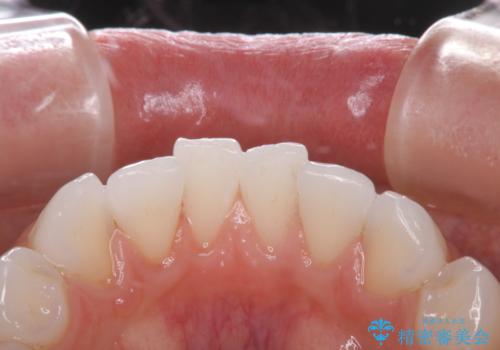

治療症例の内容

- 20代女性

- 1日

- しばらく歯科でのクリーニングをしていないため、きれいにしたいとのことでした。

PMTC30分コースを行いました。